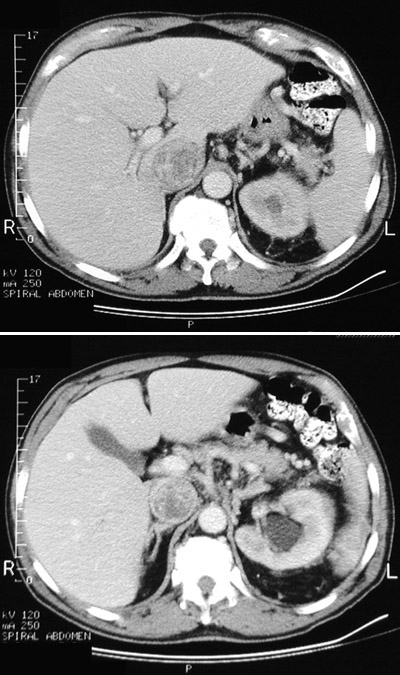

| There is invasion of a renal cell carcinoma into and up along the inferior vena cava which is distended by the neoplasm. It is possible surgically to remove such a tumor, which may even extend into the right atrium. The affected left kidney in which this neoplasm arose shows hydronephrosis in the upper pole. The upper panel is at a higher level. |